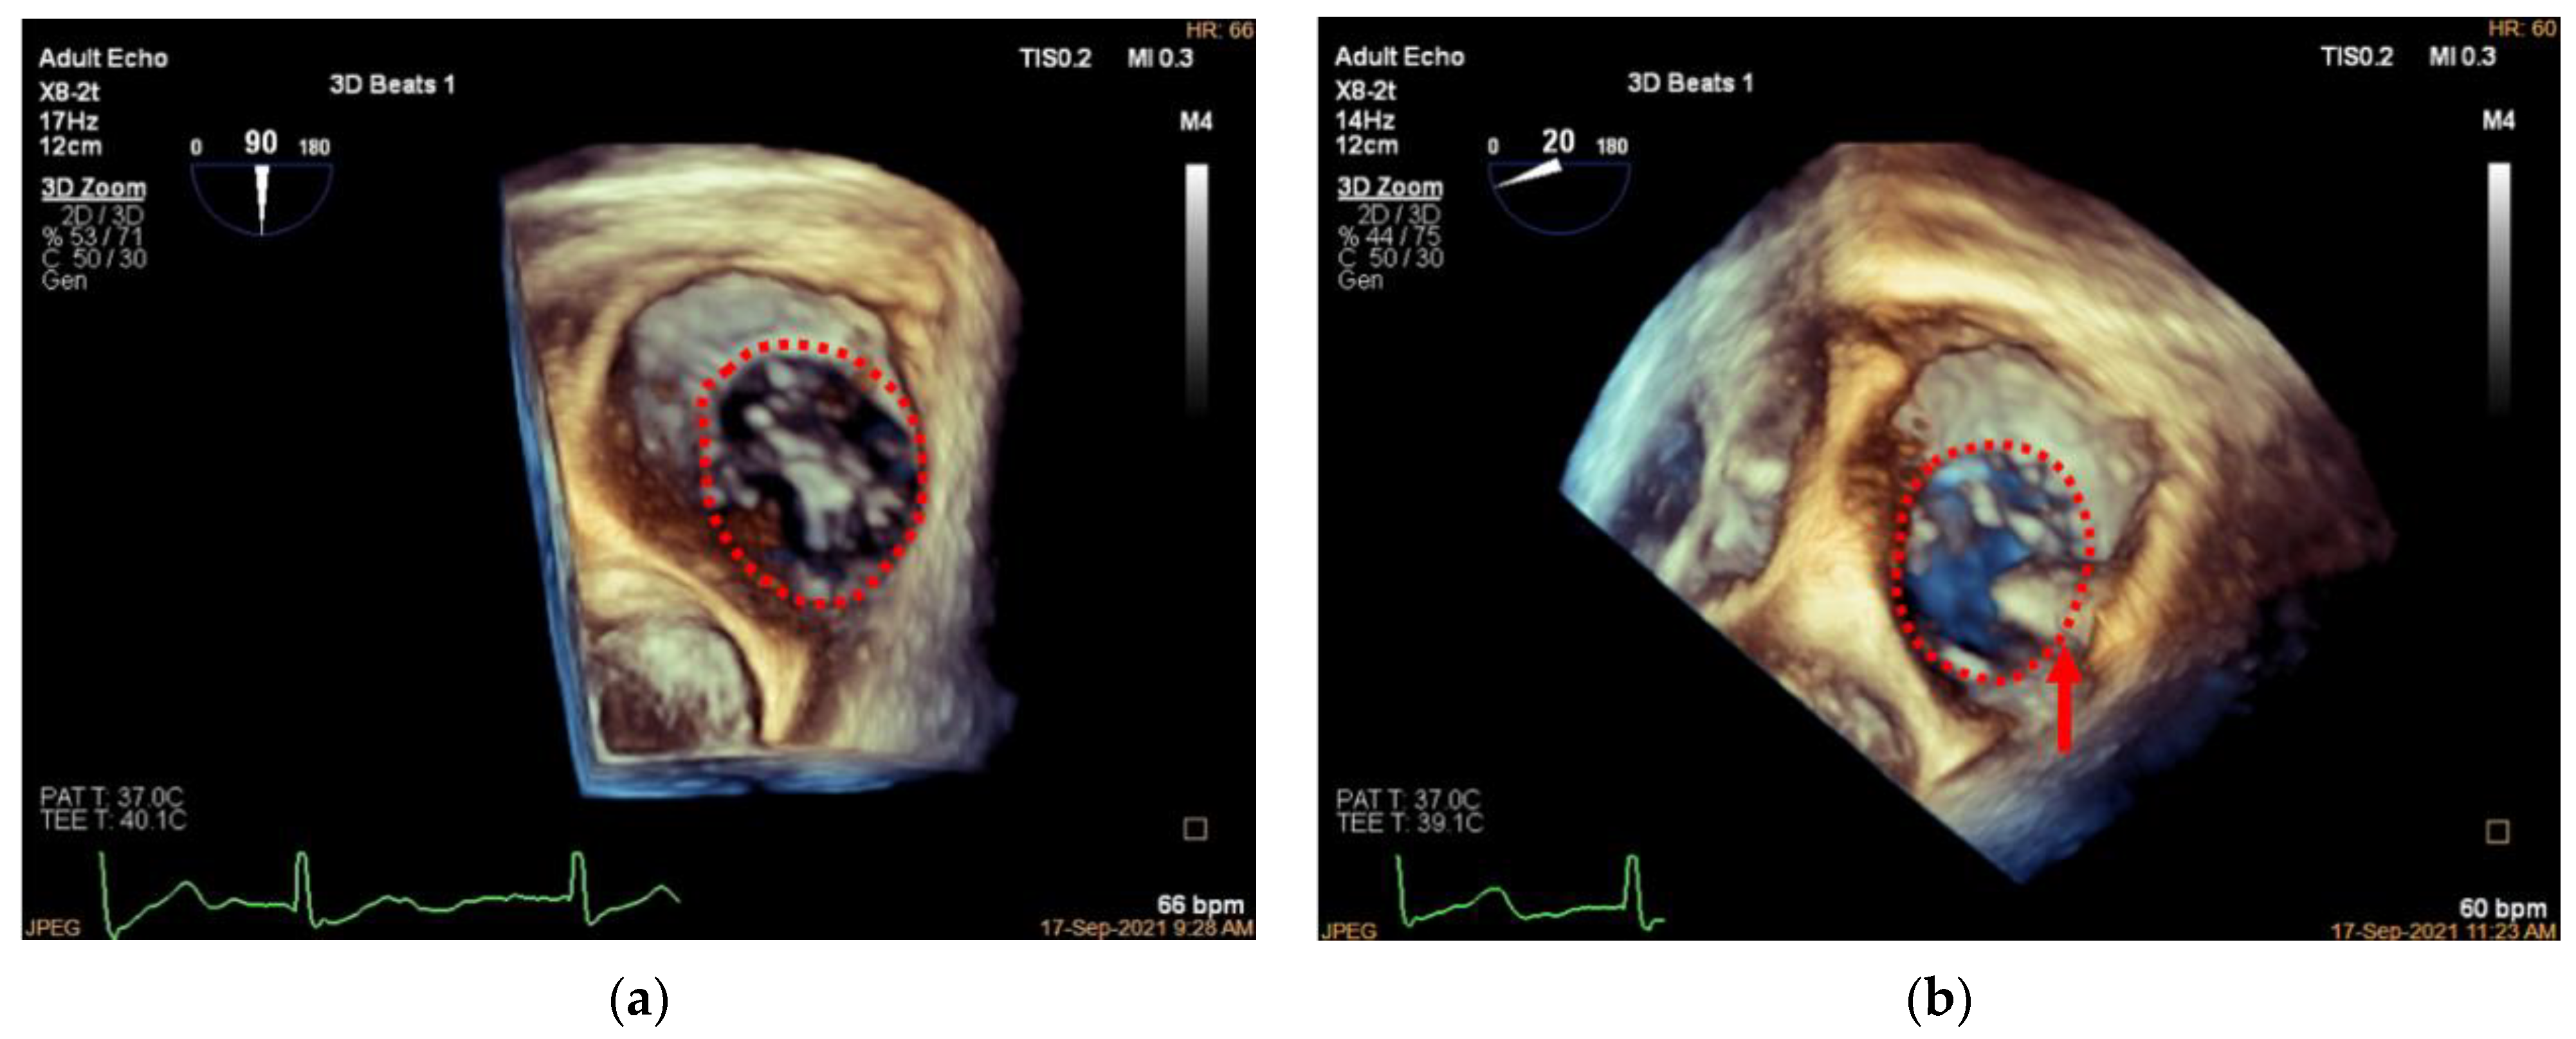

3.1. Patient Selection

3.4. Adjustment of the Clip Arm and Clamping of Annular Tissue

3.5. Valve Function Assessment